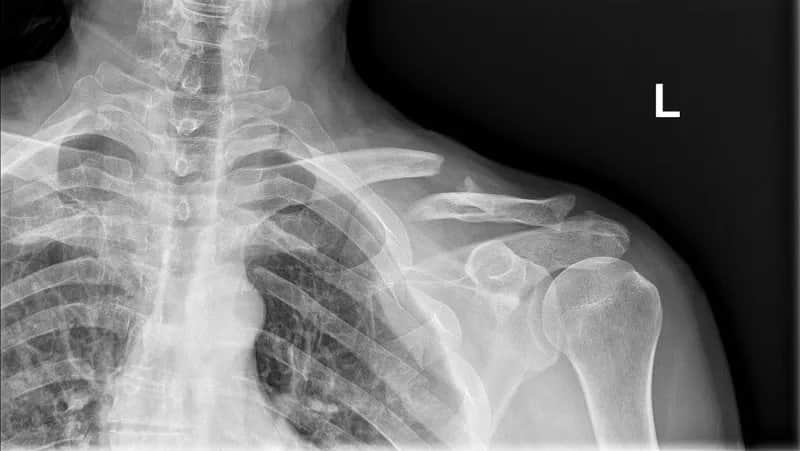

Ile trwa rehabilitacja po złamaniu obojczyka? Dowiedz się, jakie czynniki wpływają na czas powrotu do zdrowia i jak wygląda proces rehabilitacji.